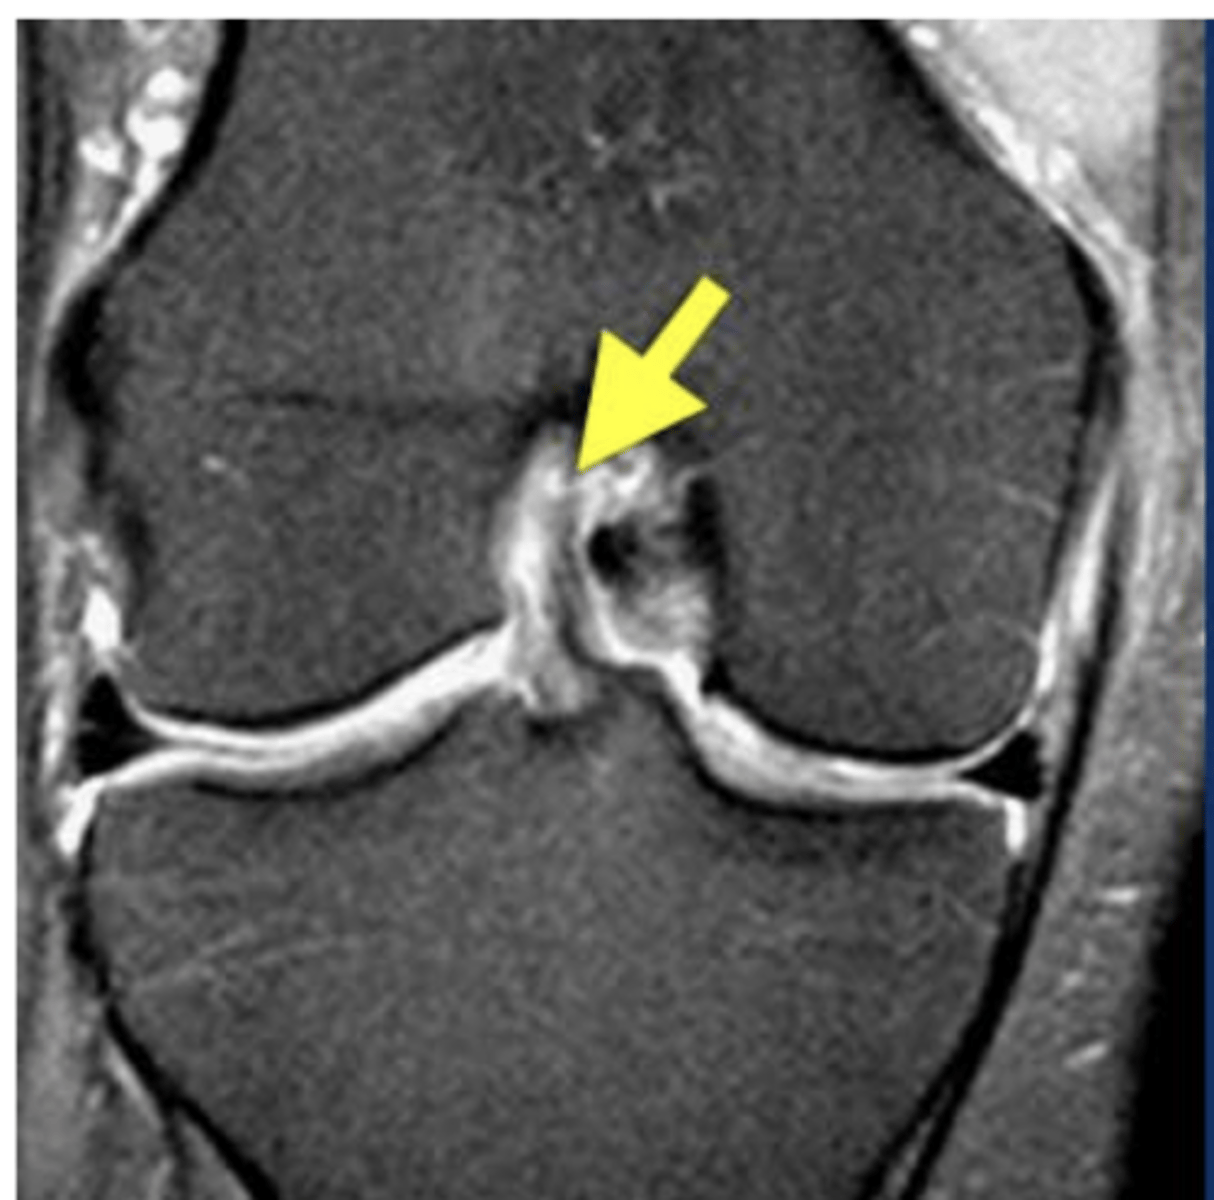

Meniscus tear (the meniscus should look like a wedge)

Define the pathology.

Meniscus tear